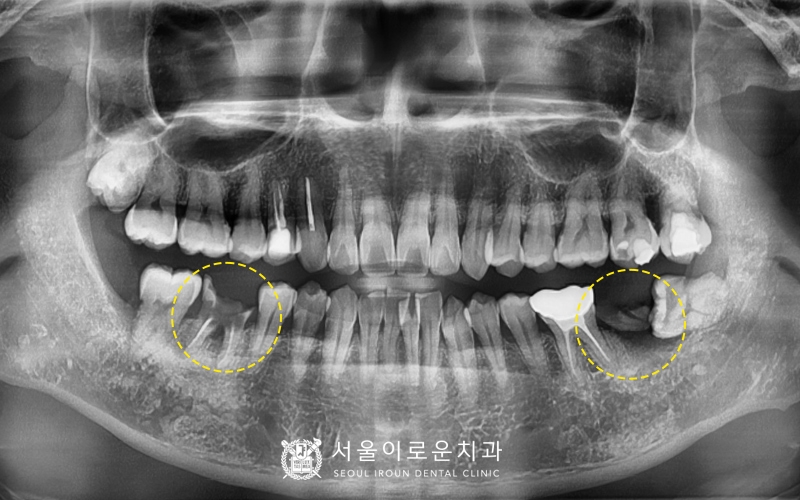

부천서울이로운치과를 찾아주신 40대

남성분의 파노라마 사진입니다.

특징적으로 눈에 띄는 것은

아래 양쪽 어금니 두개가 파절되어

부러져있는 것이었는데요.

왼쪽 아래 두번째 큰어금니(#37)는

뿌리만 남아있어 발치가 필요한 상황이었고,

오른쪽 아래 첫번째 큰 어금니(#46)는

과거 신경치료 후 크라운을 하지 않아

충치가 진행되어 이가 부러진 상태로

발치 후 뼈이식을 동반한 임플란트를

계획하기로 하였습니다~!